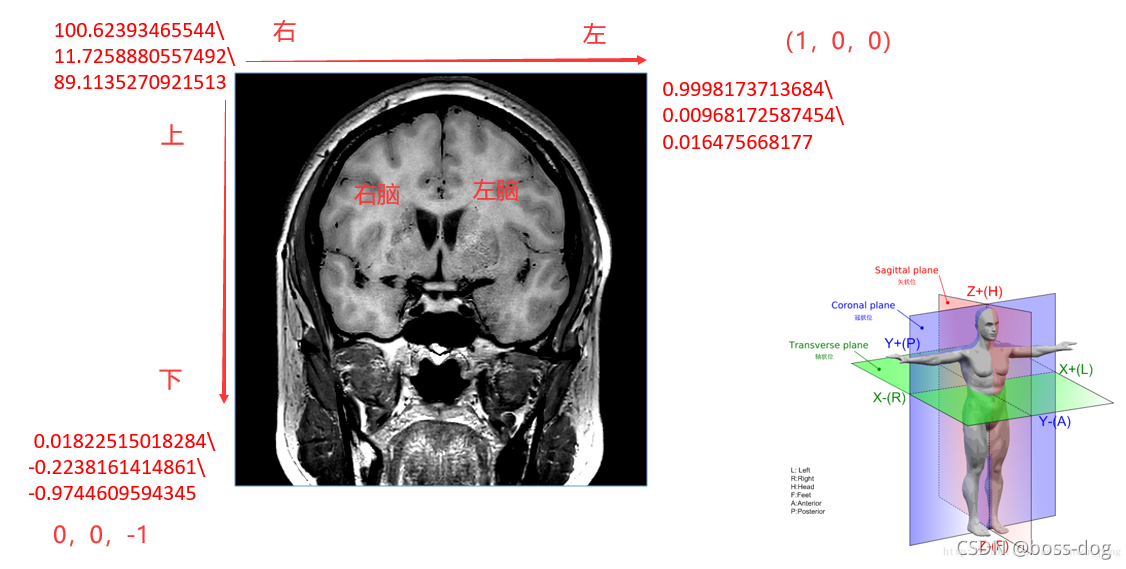

Image Orientation-5

(0020,0037) 的前三个数字代表分别代表行向量(行递增方向)和X,Y,Z轴夹角分别的余弦值(Cosine),后三个数字分别代表列向量(列递增方向)和X,Y,Z轴夹角分别的余弦值。这样就能精确计算出该张影像中每一个像素点在坐标系中的位置,对于多排螺旋CT产生的影像序列来说,这个意义尤其重大。

- 冠状面:(1,0,0)(0,0,-1)